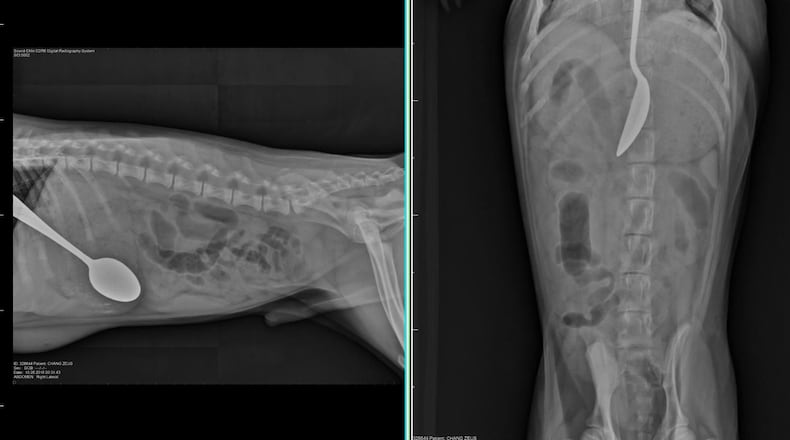

The Dunwoody resident took Zeus to Blue Pearl Veterinary Partners in Sandy Springs, and after a few X-rays, Dr. Nicolas Berryessa determined that the spoon could be removed using an endoscope, which is much less complicated than surgery.